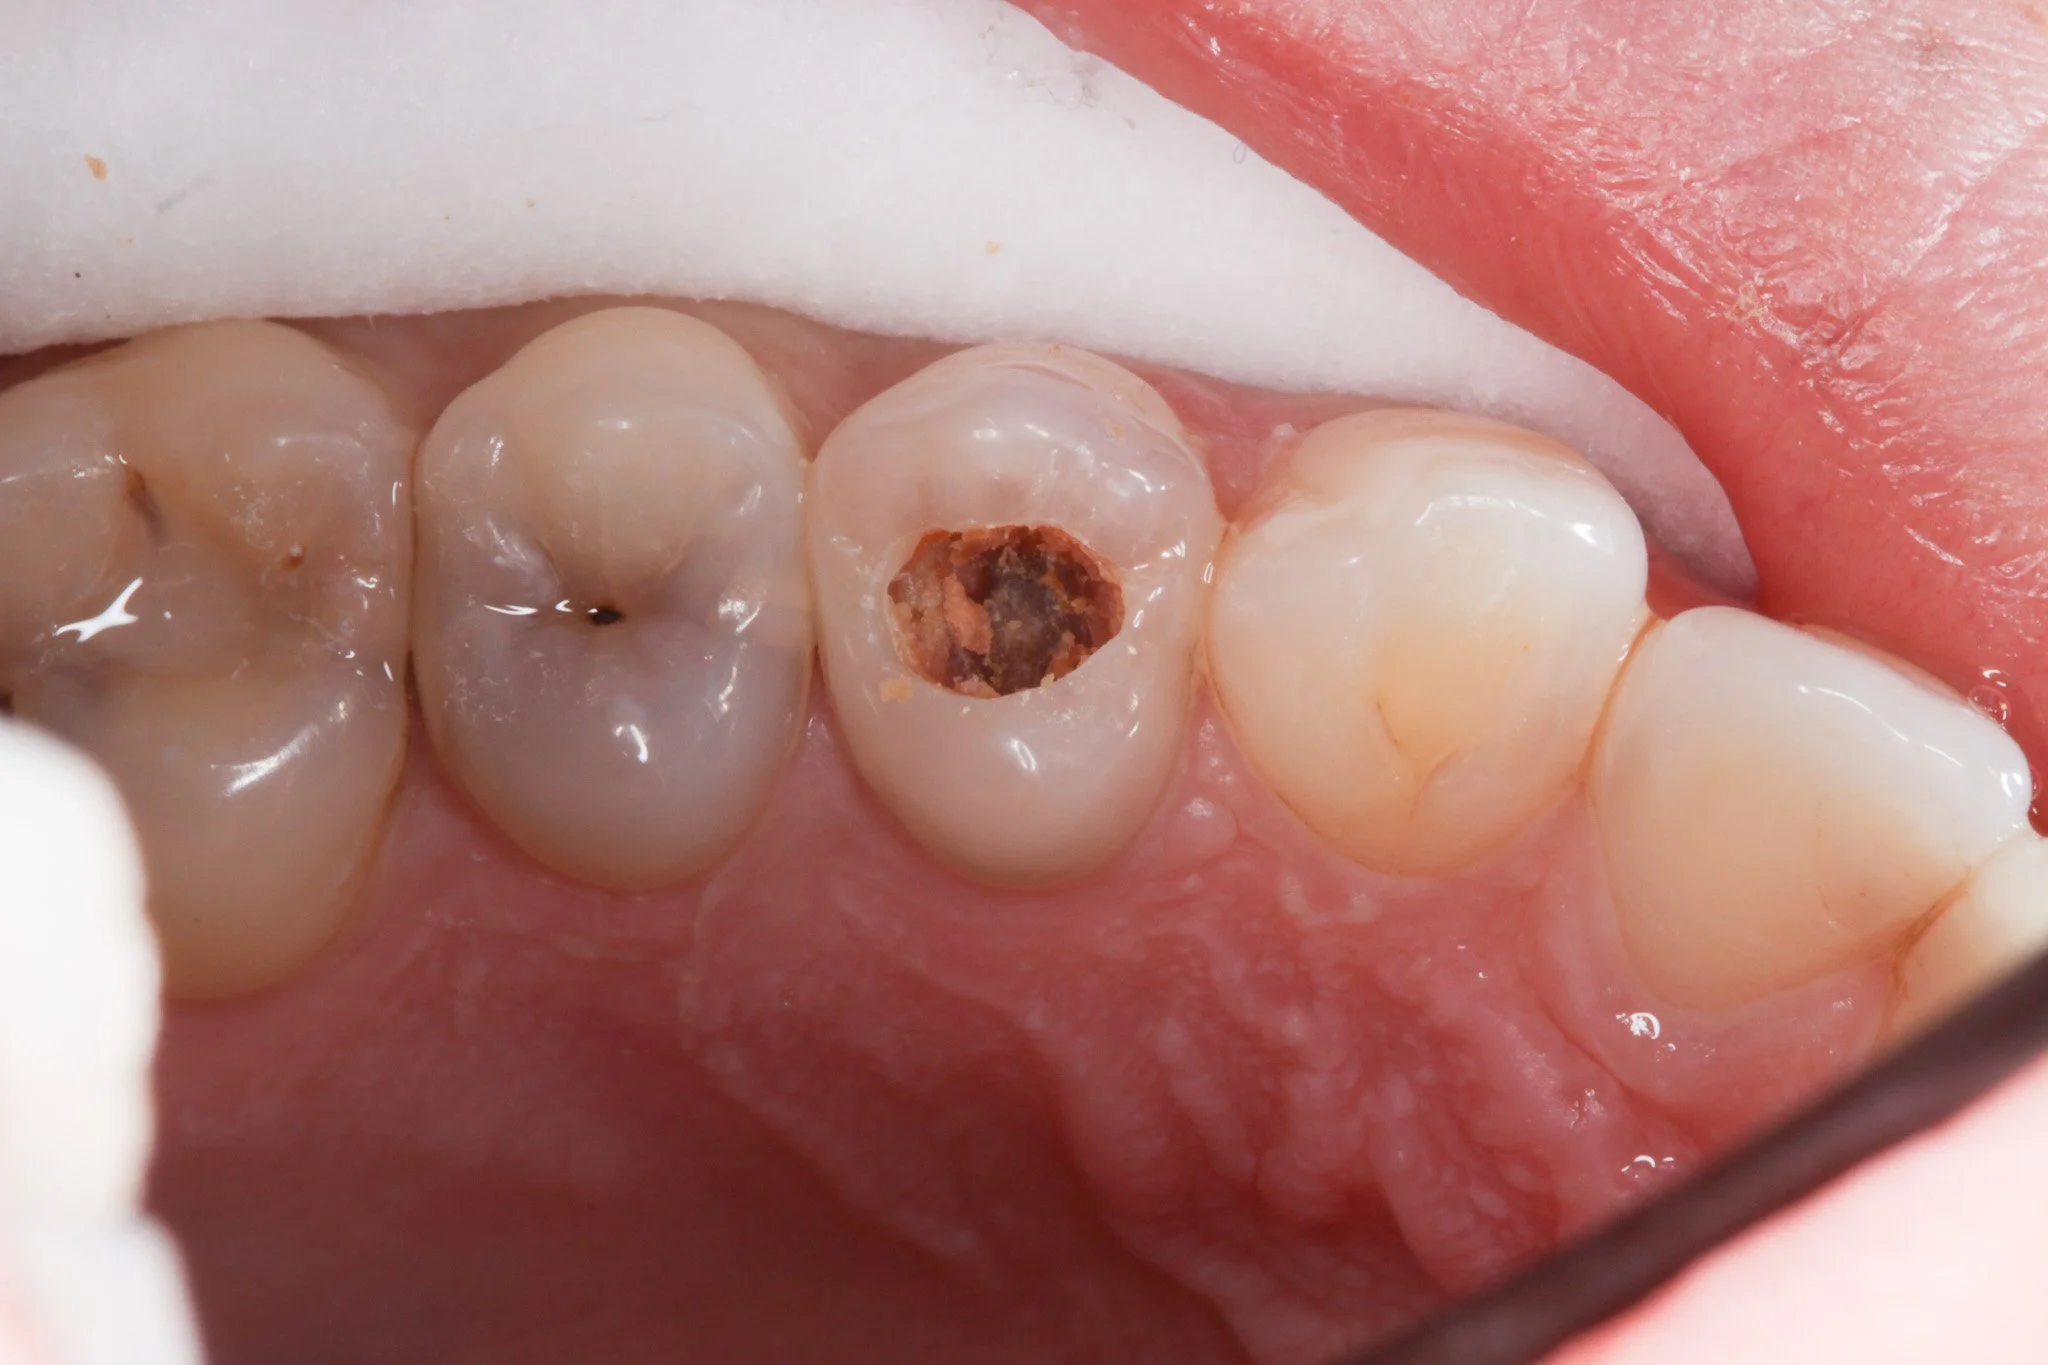

A tooth with decay

The decay is cleared away, leaving a hole

The hole is filled with a tooth-coloured composite resin